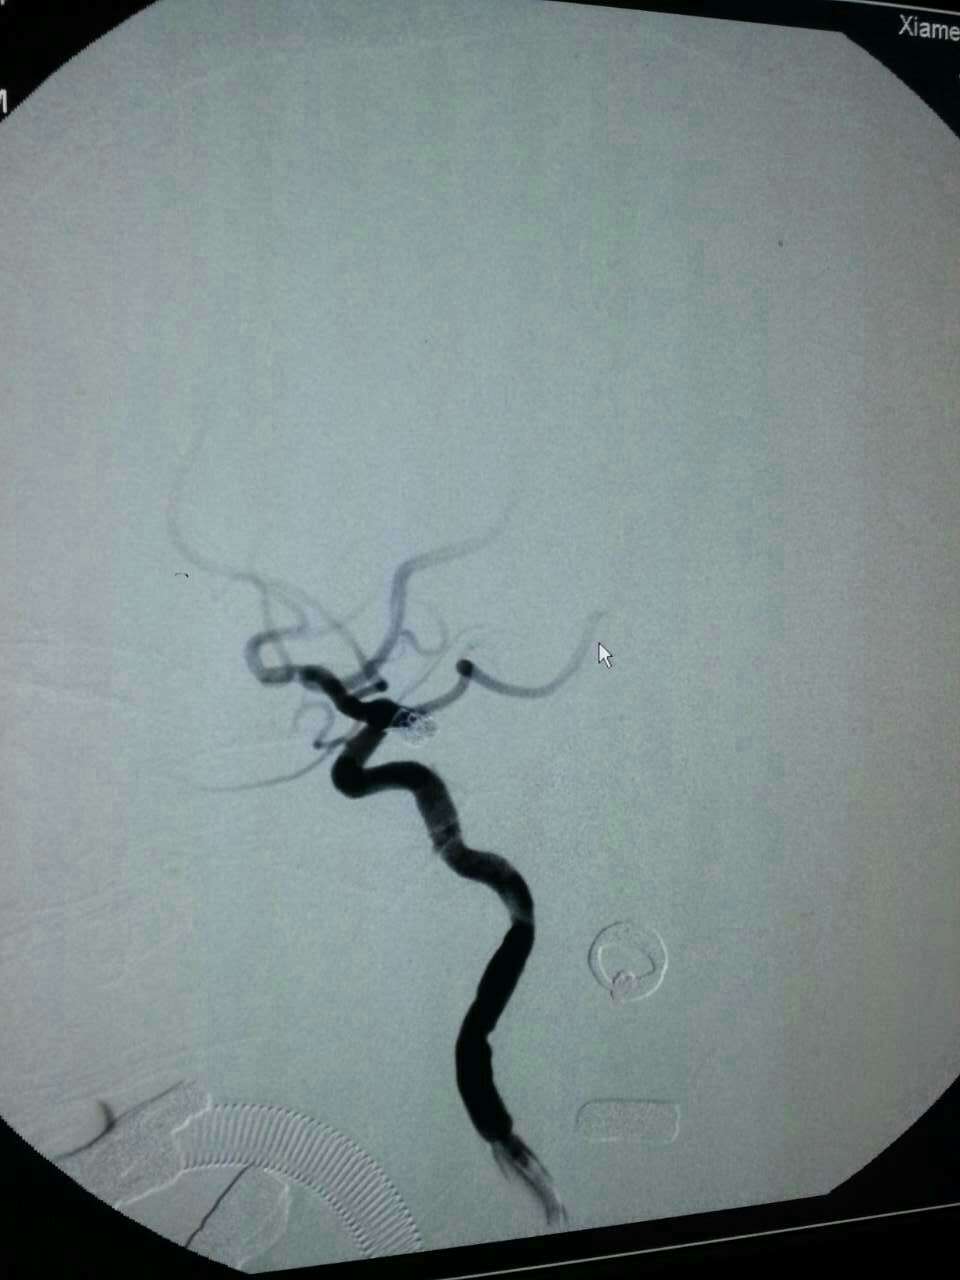

厦门第三医院神经外科每年应用介入栓塞技术抢救颅内动脉瘤破裂患者上百例。昨天晚上,陈金龙副主任医师、何雪阳等技术团队又成功抢救来自同安莲花一位80岁叶女士,大量蛛网膜下腔出血,手术顺利,现患者已清醒,可自行进食。